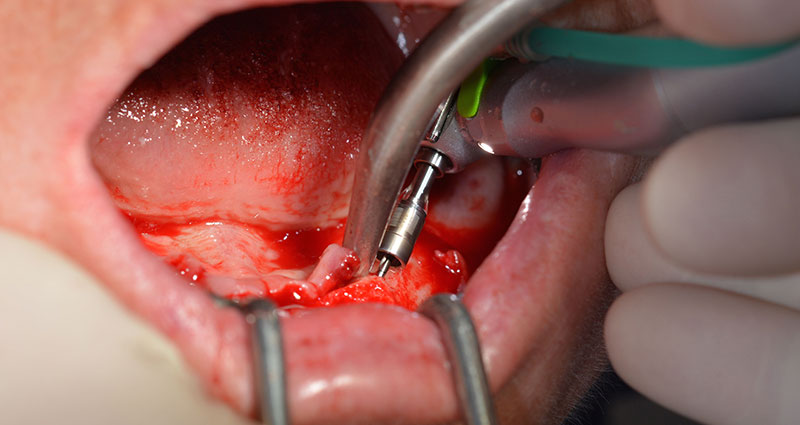

Procedimiento quirúrgico

Tras la extracción de la dentición residual en el maxilar inferior, se realizó la incisión crestal en la región comprendida entre la pieza dental 37 y la 47.

A continuación, se identificó el agujero mentoniano (foramen mentale) como la estructura anatómica límite y se alisó el cortical de la cresta ósea con la pieza de mano recta y una fresa redonda grande (fig. 4).